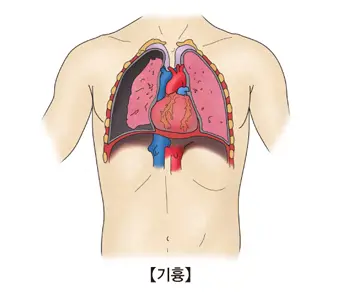

폐기흉 증상 알고 계신가요? 폐기흉은 폐와 가슴벽 사이에 공기가 차서 폐가 제대로 팽창하지 못하는 상태를 의미합니다. 이로 인해 호흡이 힘들어지고 심한 경우 응급 상황으로 이어질 수 있습니다. 오늘은 폐기흉 증상 원인과 치료, 폐기흉 수술 비용 및 군대 면제까지 알아보겠습니다.

폐는 풍선처럼 숨을 들이마시면 부풀고, 내쉬면 줄어듭니다. 그런데 풍선이 들어 있어야 할 자리에 바람이 새어 나와서 주변 공간(폐와 가슴벽 사이 공간)에 차게 되면, 풍선이 제대로 부풀지 못합니다. 이게 바로 폐기흉입니다. 쉽게 말해, “폐에 바람이 새서 숨을 잘 못 쉬게 되는 상태”라고 할 수 있습니다.

폐기흉은 자연 발생하는 경우도 있으며 외상이나 의료 시술 중 발생하는 경우도 있습니다. 특히 긴장성 폐기흉은 응급 상황으로 즉각적인 조치가 필요합니다. 이처럼 기전과 발생 상황에 따라 폐기흉은 임상적 의미가 크게 달라집니다.